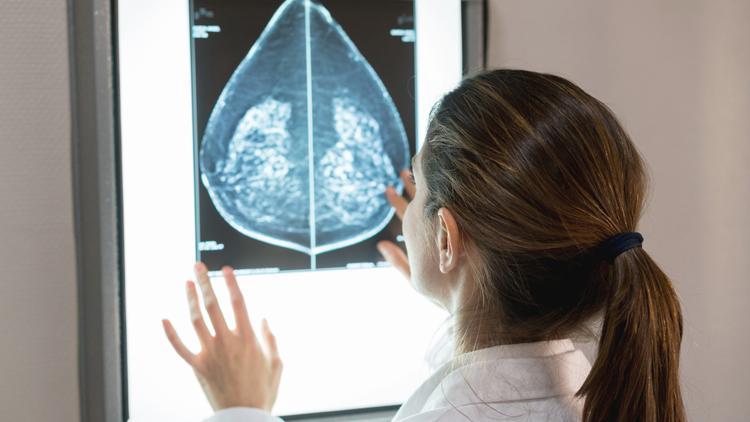

Meme kanserinde erken tanı hayat kurtarıyor

Meme kanserinde erken tanının hayat kurtardığına dikkat çeken Radyasyon Onkolojisi Uzmanı Dr. Öğr. Üyesi Ayşe Okumuş, günümüzdeki meme kanseri tedavileri hakkında önemli bilgiler verdi.

Kadınlarda en sık görülen kanser türü meme kanseridir. Her sekiz kadından birinde meme kanseri ile karşılaşmaktayız. Aile öyküsü ve 50 yaş üzeri olmak riski arttırır. Ailede meme kanseri olması riskini %30-80 arttırır, bu nedenle bu grubun daha bilinçli olması gerekir. Meme kanserini erken yakalamak tamamen size bağlıdır. Burada kendi kendine meme muayenesi tümörü erken evrede tespit etmemizi sağlar.

Meme kanseri en sık memede kitle ile karşımıza çıkar ayrıca memede asimetri meme cildinde kızarıklık, şişlik, koltuk altında kitle şeklinde bulgu verebilir.

Eskiden tüm meme cerrahi olarak çıkarılırdı ve sonrasında bazı faktörlere bağlı olarak kemoterapi ve radyoterapi uygulanırdı. Güncel tedavi yaklaşımımız meme koruyucu olarak adlandırılan sadece tümörün alınmasıdır. Meme koruyucu cerrahide ilave olarak gözle görülemeyen tümör hücreleri ve geri kalan meme dokusu ışınlanarak organ koruması sağlanmaktadır.